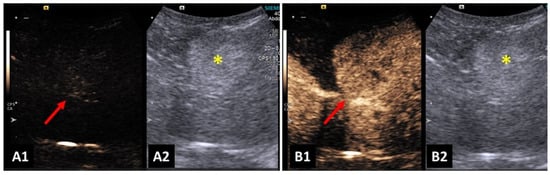

4. Applicability of CEUS

4.1. Male Reproductive Tract

4.3. Kidneys and Urinary Bladder

4.5. Spleen